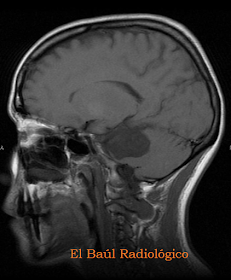

FIGURA 11-A) No son frecuentes los quistes epidermoides en el compartimento supratentorial, pero también puede encontrase alguno.

FIGURA 11-B) Imagen FSE-T1.

FIGURA 11-C) Imagen FLAIR-T2. Aspecto "grumoso" característico del quiste, delimitado por una delgada cápsula. Es extraparenquimatoso y erosiona la tabla interna del díploe. Podría confundirse con un meninigioma.

FIGURA 11-E)Imagen FSE-Dp.

FIGURA 11-F) Imagen FSE-Dp.

FIGURA 11-G) Imagen SE-DWI. El brillo intenso de la lesión descarta la posibilidad de que sea un meningioma.

FIGURA 11-H) Imagen FSE-T1 co Gadolinio. Tampoco se realza con contraste.

FIGURA 11-I) Control postquirúrgico. En esta localización el tratamiento quirúrgico es muy efectivo, en los restantes casos que infiltran las estructuras anatómicas de la fosa posterior la resección total de los quistes resulta una tarea árdua, casi imposible.